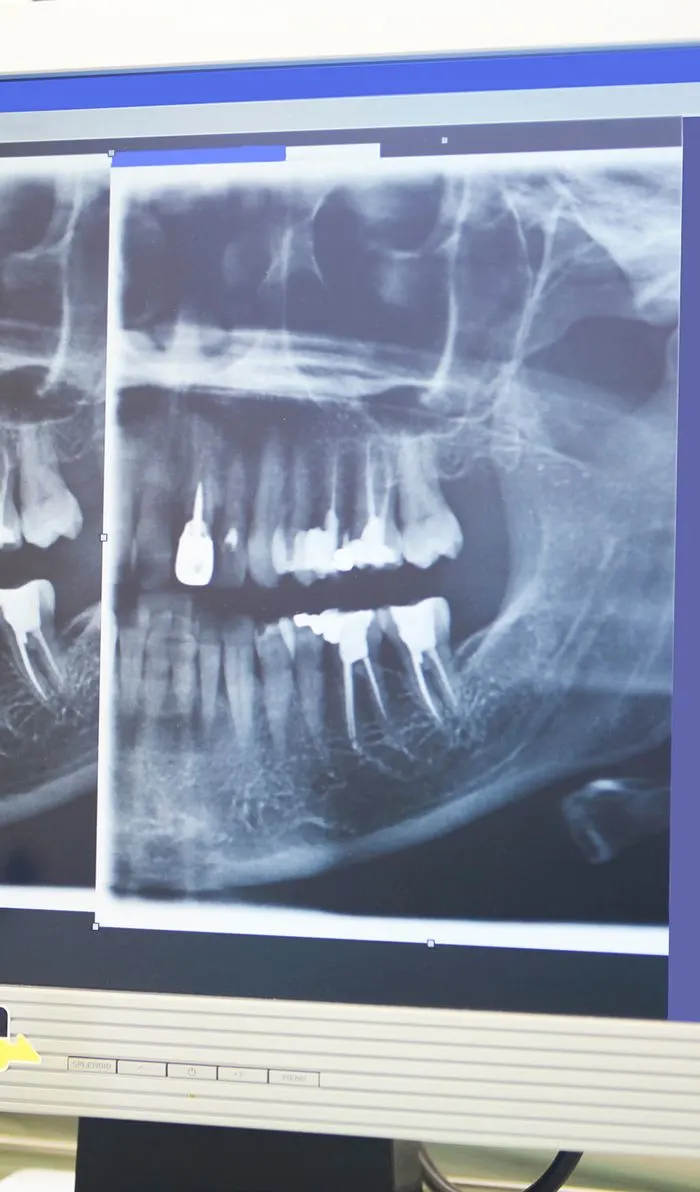

Digital Imaging

Advanced digital imaging techniques have taken the guesswork out of root canal therapy, resulting in a quicker, more efficient procedure with less pain and discomfort than ever before.

X-ray

Your dentist will begin with a comprehensive examination of your tooth and x-rays to identify the cause of your dental discomfort. If an infection is present, they'll assess its severity to determine if a root canal is the appropriate treatment option.If root canal therapy is necessary, your dentist will ensure the treatment area is completely numb, including the nerves. Before starting the procedure, they'll discuss various sedation options with you to ensure your comfort throughout the treatment.